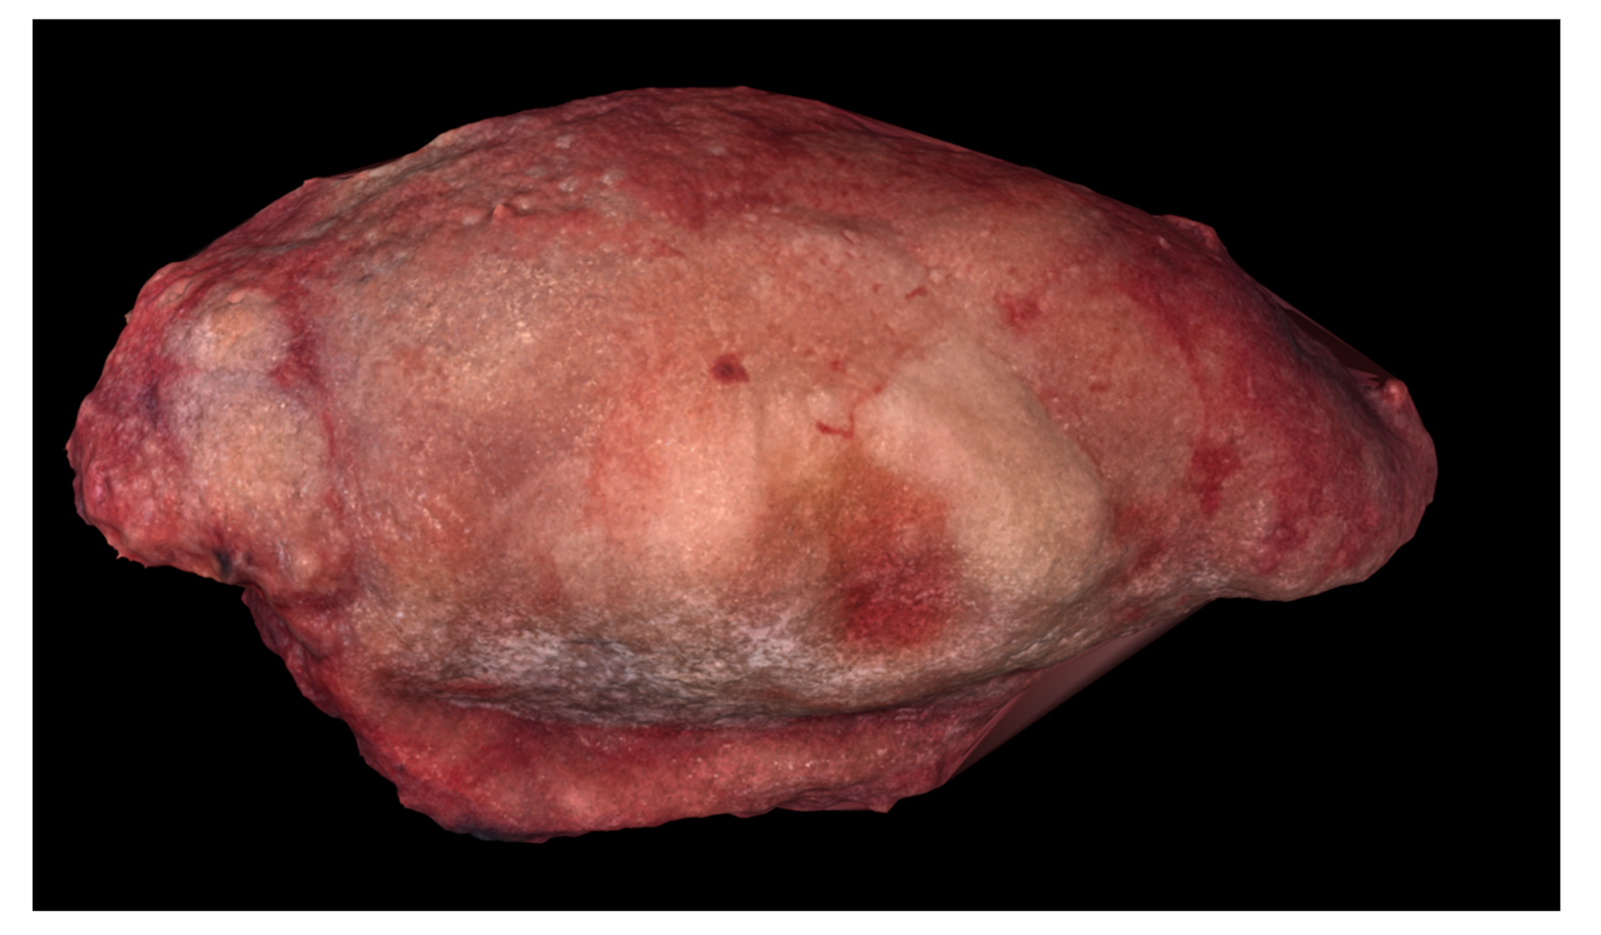

A 53-year-old female was diagnosed with a p16-negative T3N2bM0, Stage IVa SCC of the mobile tongue at an outside institution (Figure 2 and Figure 3). Hemiglossectomy was performed in conjunction with neck dissection of levels I, IIa, III, and IV on the right side. Anterolateral thigh microvascular flap was utilized in reconstruction. Histopathology revealed an SCC with a diameter of 24 mm and with 10 mm depth of invasion. The minimum resection margin was 7 mm on the medial edge of the tumor. She had two metastatic lymph nodes in level IIa with no extranodal extension. The pathological staging was pT2pN2bM0 (Stage IVa). MDTB recommended postoperative chemoradiotherapy.

Figure 2.

Preoperative image of Case 2 showing squamous cell carcinoma of the right mobile tongue.